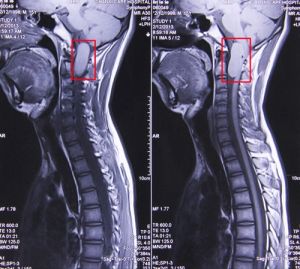

3.CT、MRI掃描:由於脊髓髓內腫瘤症狀缺乏特異性,診斷主要依靠影像學檢查。CT、MRI問世前,常常依靠脊柱平片和脊髓造影診斷診斷既困難又會加重病情MRI的出現使髓內腫瘤能夠早期簡便、確實地得到診斷病理性質不同,影像學特徵也有所不同:

(1)星形細胞瘤:常見於10~50歲,占椎管內腫瘤的6%~8%,最常發生於頸段和胸段脊髓多數為良性,約7.5%多數星形細胞瘤單獨發生,Ⅰ型神經纖維瘤病常合併星形細胞瘤組織學形態常有2種類型:浸潤生長的星形細胞瘤和局限生長的星形細胞瘤MRI常無特徵性改變T1示受累脊髓廣泛增粗,可以有高信號(出血)或低信號(囊變)混雜。T2常為高信號。增強後可見腫瘤強化,並可見到與水腫帶的分界。部分星形細胞瘤無強化,生長越緩慢的腫瘤強化越不明顯。腫瘤增強程度與病變區域血流增加和脊髓屏障破壞有關也就是說與腫瘤良性程度有關。星形細胞瘤增強常不規則且呈多樣性,腫瘤增強對活檢和手術有幫助。增強掃描有助於鑑別囊性腫瘤和脊髓良性囊腫有報導,脊髓囊腫發生於腫瘤內者13%,鄰近腫瘤者74%鄰近腫瘤的囊腫液清亮囊壁為膠質細胞,而腫瘤內囊變囊液為血性或高蛋白液呈橙色鄰近腫瘤的囊變不強化提示為非腫瘤性囊變。星形細胞瘤可同時存在新鮮和陳舊出血,其影像學表現與出血時間有關急性出血(3天之內)T2像為低信號,3~7天 T1像主要以高信號為主,T2像常為混雜信號組織學上,惡性星形細胞瘤富於血管與脊髓無邊界所以手術中辨認腫瘤-脊髓邊界困難。

(2)室管膜瘤:好發年齡為40~50歲,可發生於脊髓任何部位以胸段和頸段最常見影像學表現與星形細胞瘤有一定程度的區別,腫瘤上端及尾端合併囊變是常見的標誌但腫瘤內囊變少見MRI為較均勻強化,或混雜信號部分病例腫瘤可突出至脊髓表面甚至達蛛網膜下腔。